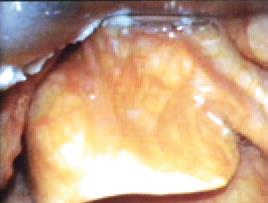

La introducción de la pala en la cavidad bucal debe hacerse con cuidado y bajo visión directa de las estructuras conforme avanzamos para así minimizar el riesgo de lesiones traumáticas. Debido a la visión panorámica posicionaremos la punta de la pala en la vallécula, en el caso de utilizar una pala tipo Macintosh, bajo visión directa, o calzando la epiglotis por su cara dorsal si utilizamos una pala tipo Miller o en aquellos casos en que utilizando la pala de Macintosh ( especialmente el nº4) nos encontramos ante situaciones en las que esta maniobra nos sea de utilidad, fundamentalmente 2 casos:

Laringoscopia tipo Macintosh. Imagen cortesia del Dr. José Guzmán Olivares, miembro comité VAD CLASA